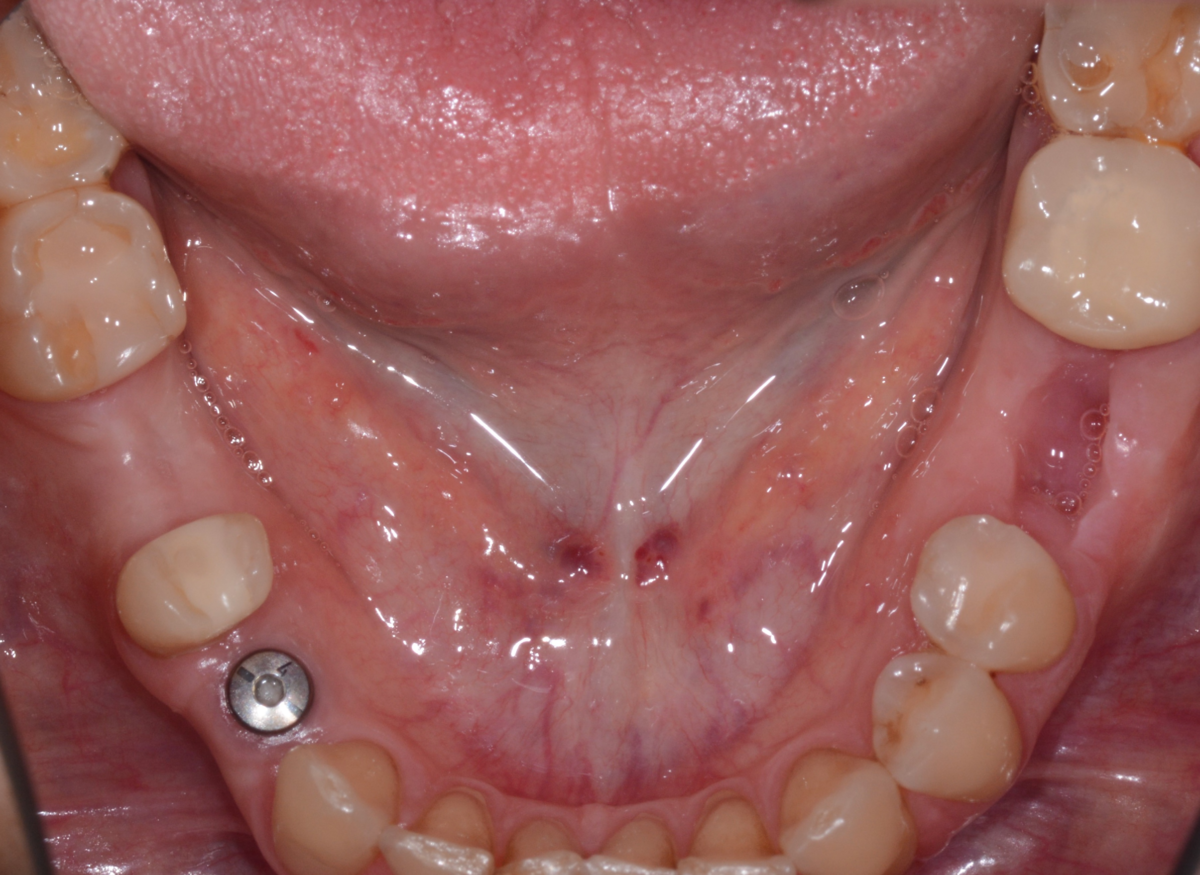

Были установлены имплантаты. Пока длилось хирургическое лечение (около 6 месяцев), у пациентки было достаточно времени определиться, что же она хочет по эстетике - отбеливание или виниры.

Была проведена тотальная реконструкция прикуса, так как присутствовала стираемость на передних зубах, а на боковых зубах стояли несколько коронок и достаточно большие пломбы. Цель заключалась улучшить не только эстетическую составляющую , но и функциональную, поэтому требовалось протезирование боковых отделов для надёжного и долгосрочного результата лечения.